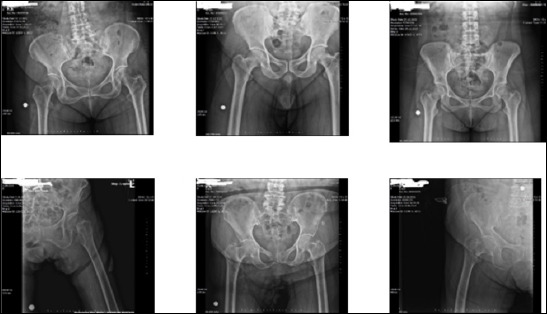

Methods: The study was conducted on a total of 598 plain pelvic X-ray images, including 296 patients with femoral neck fractures and 302 individuals without femoral neck fractures. Initially, transfer learning was applied using pre-trained deep learning models: VGG-16, ResNet-50, and MobileNetv2.

背景:股骨颈骨折是一个严重的健康问题,尤其是在老年人中。本研究的目的是利用深度学习和机器学习算法从骨盆x线平片诊断和分类股骨颈骨折,并比较这些方法的性能。方法:对598张骨盆x线平片进行研究,其中股骨颈骨折患者296例,非股骨颈骨折患者302例。最初,迁移学习应用于预训练的深度学习模型:VGG-16、ResNet-50和MobileNetv2。结果:预训练的VGG-16网络在股骨颈骨折检测和分类方面的性能略优于ResNet-50和MobileNetV2。采用VGG-16模型,准确率95.6%,灵敏度95.5%,特异性93.3%,精密度95.7%,F1评分95.5%,Cohen’s kappa为0.91,受试者工作特征(ROC)曲线为0.99。随后,使用常见的机器学习算法对VGG-16的卷积层提取的特征进行分类。其中,k近邻(k-NN)算法优于其他算法,比VGG-16模型的准确率高出1%。结论:采用深度学习和机器学习方法对股骨颈骨折进行检测和分类,取得了成功的结果。该模型可通过多中心研究进一步完善。所提出的模型对于在急诊科工作的医生和那些在评估骨盆平片方面没有足够经验的医生可能特别有用。